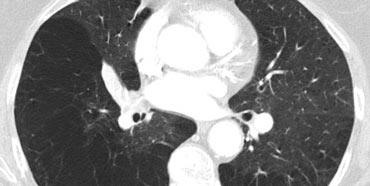

Ca lâm sàng minh họa: Phù phổi do tim

Hình ảnh: Chụp CT được thực hiện để loại trừ thuyên tắc phổi phát hiện sự kết hợp giữa dày vách đều, nhẵn và mờ kính mờ phân bố theo trọng lực.

Chẩn đoán là phù phổi do tim.

Đặc điểm chính của phù phổi do tim:

- Thường biểu hiện với dày vách liên tiểu thùy kết hợp mờ kính mờ.

- Phân bố quanh rốn phổi và theo trọng lực là đặc trưng của phù phổi thủy tĩnh.

- Các dấu hiệu bổ sung có thể bao gồm:

- Dày mô kẽ quanh phế quản-mạch máu (“viền quanh phế quản”)

- Dày rãnh liên thùy

- Tim to

- Tràn dịch màng phổi

- Mặc dù HRCT không được sử dụng thường quy để chẩn đoán (các dấu hiệu lâm sàng và X-quang thường đủ để kết luận), phù phổi thủy tĩnh không nghi ngờ trước đôi khi có thể được phát hiện tình cờ.